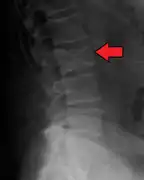

Illustration showing the most common site of bone lesions in vertebrae

Bone pain affects almost 70% of people with multiple myeloma and is one of the most common symptoms.[2]:653[22] Myeloma bone pain usually involves the spine and ribs, and worsens with activity. Persistent, localized pain may indicate a pathological bone fracture. Involvement of the vertebrae may lead to spinal cord compression or kyphosis. Myeloma bone disease is due to the overexpression of receptor activator for nuclear factor κ B ligand (RANKL) by bone marrow stroma. RANKL activates osteoclasts, which resorb bone. The resultant bone lesions are lytic (cause breakdown) in nature, and are best seen in plain radiographs, which may show "punched-out" resorptive lesions (including the "raindrop" appearance of the skull on radiography). The breakdown of bone also leads to the release of calcium ions into the blood, leading to hypercalcemia and its associated symptoms.[23]

The diagnostic examination of a person with suspected multiple myeloma typically includes a skeletal survey. This is a series of X-rays of the skull, axial skeleton, and proximal long bones. Myeloma activity sometimes appears as "lytic lesions" (with local disappearance of normal bone due to resorption) or as "punched-out lesions" on the skull X-ray ("raindrop skull"). Lesions may also be sclerotic, which is seen as radiodense.[70] Overall, the radiodensity of myeloma is between −30 and 120 Hounsfield units (HU).[71] Magnetic resonance imaging is more sensitive than simple X-rays in the detection of lytic lesions, and may supersede a skeletal survey, especially when vertebral disease is suspected. Occasionally, a CT scan is performed to measure the size of soft-tissue plasmacytomas. Nuclear Medicine Bone scans are typically not of any additional value in the workup of people with myeloma (no new bone formation; lytic lesions not well visualized on nuclear bone scan).